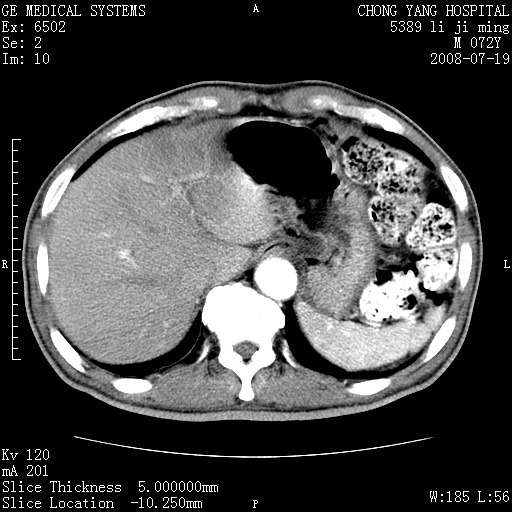

以下是引用zjzjr在2008-7-19 20:57:00的发言:[br]胰头增大,边缘模糊,周围可见渗出影,右侧肾前筋膜增厚.支持胰腺炎.

以下是引用yangyudong333在2008-7-20 6:56:00的发言:[br]胰腺增大尤以胰头明显,边缘模糊,周围可见渗出影,右侧肾前筋膜增厚,肠管於涨.支持胰腺炎

以下是引用不学无术在2008-7-19 23:15:00的发言:[br]胰腺增大尤以胰头明显,边缘模糊,周围可见渗出影,右侧肾前筋膜增厚,肠管於涨.支持胰腺炎